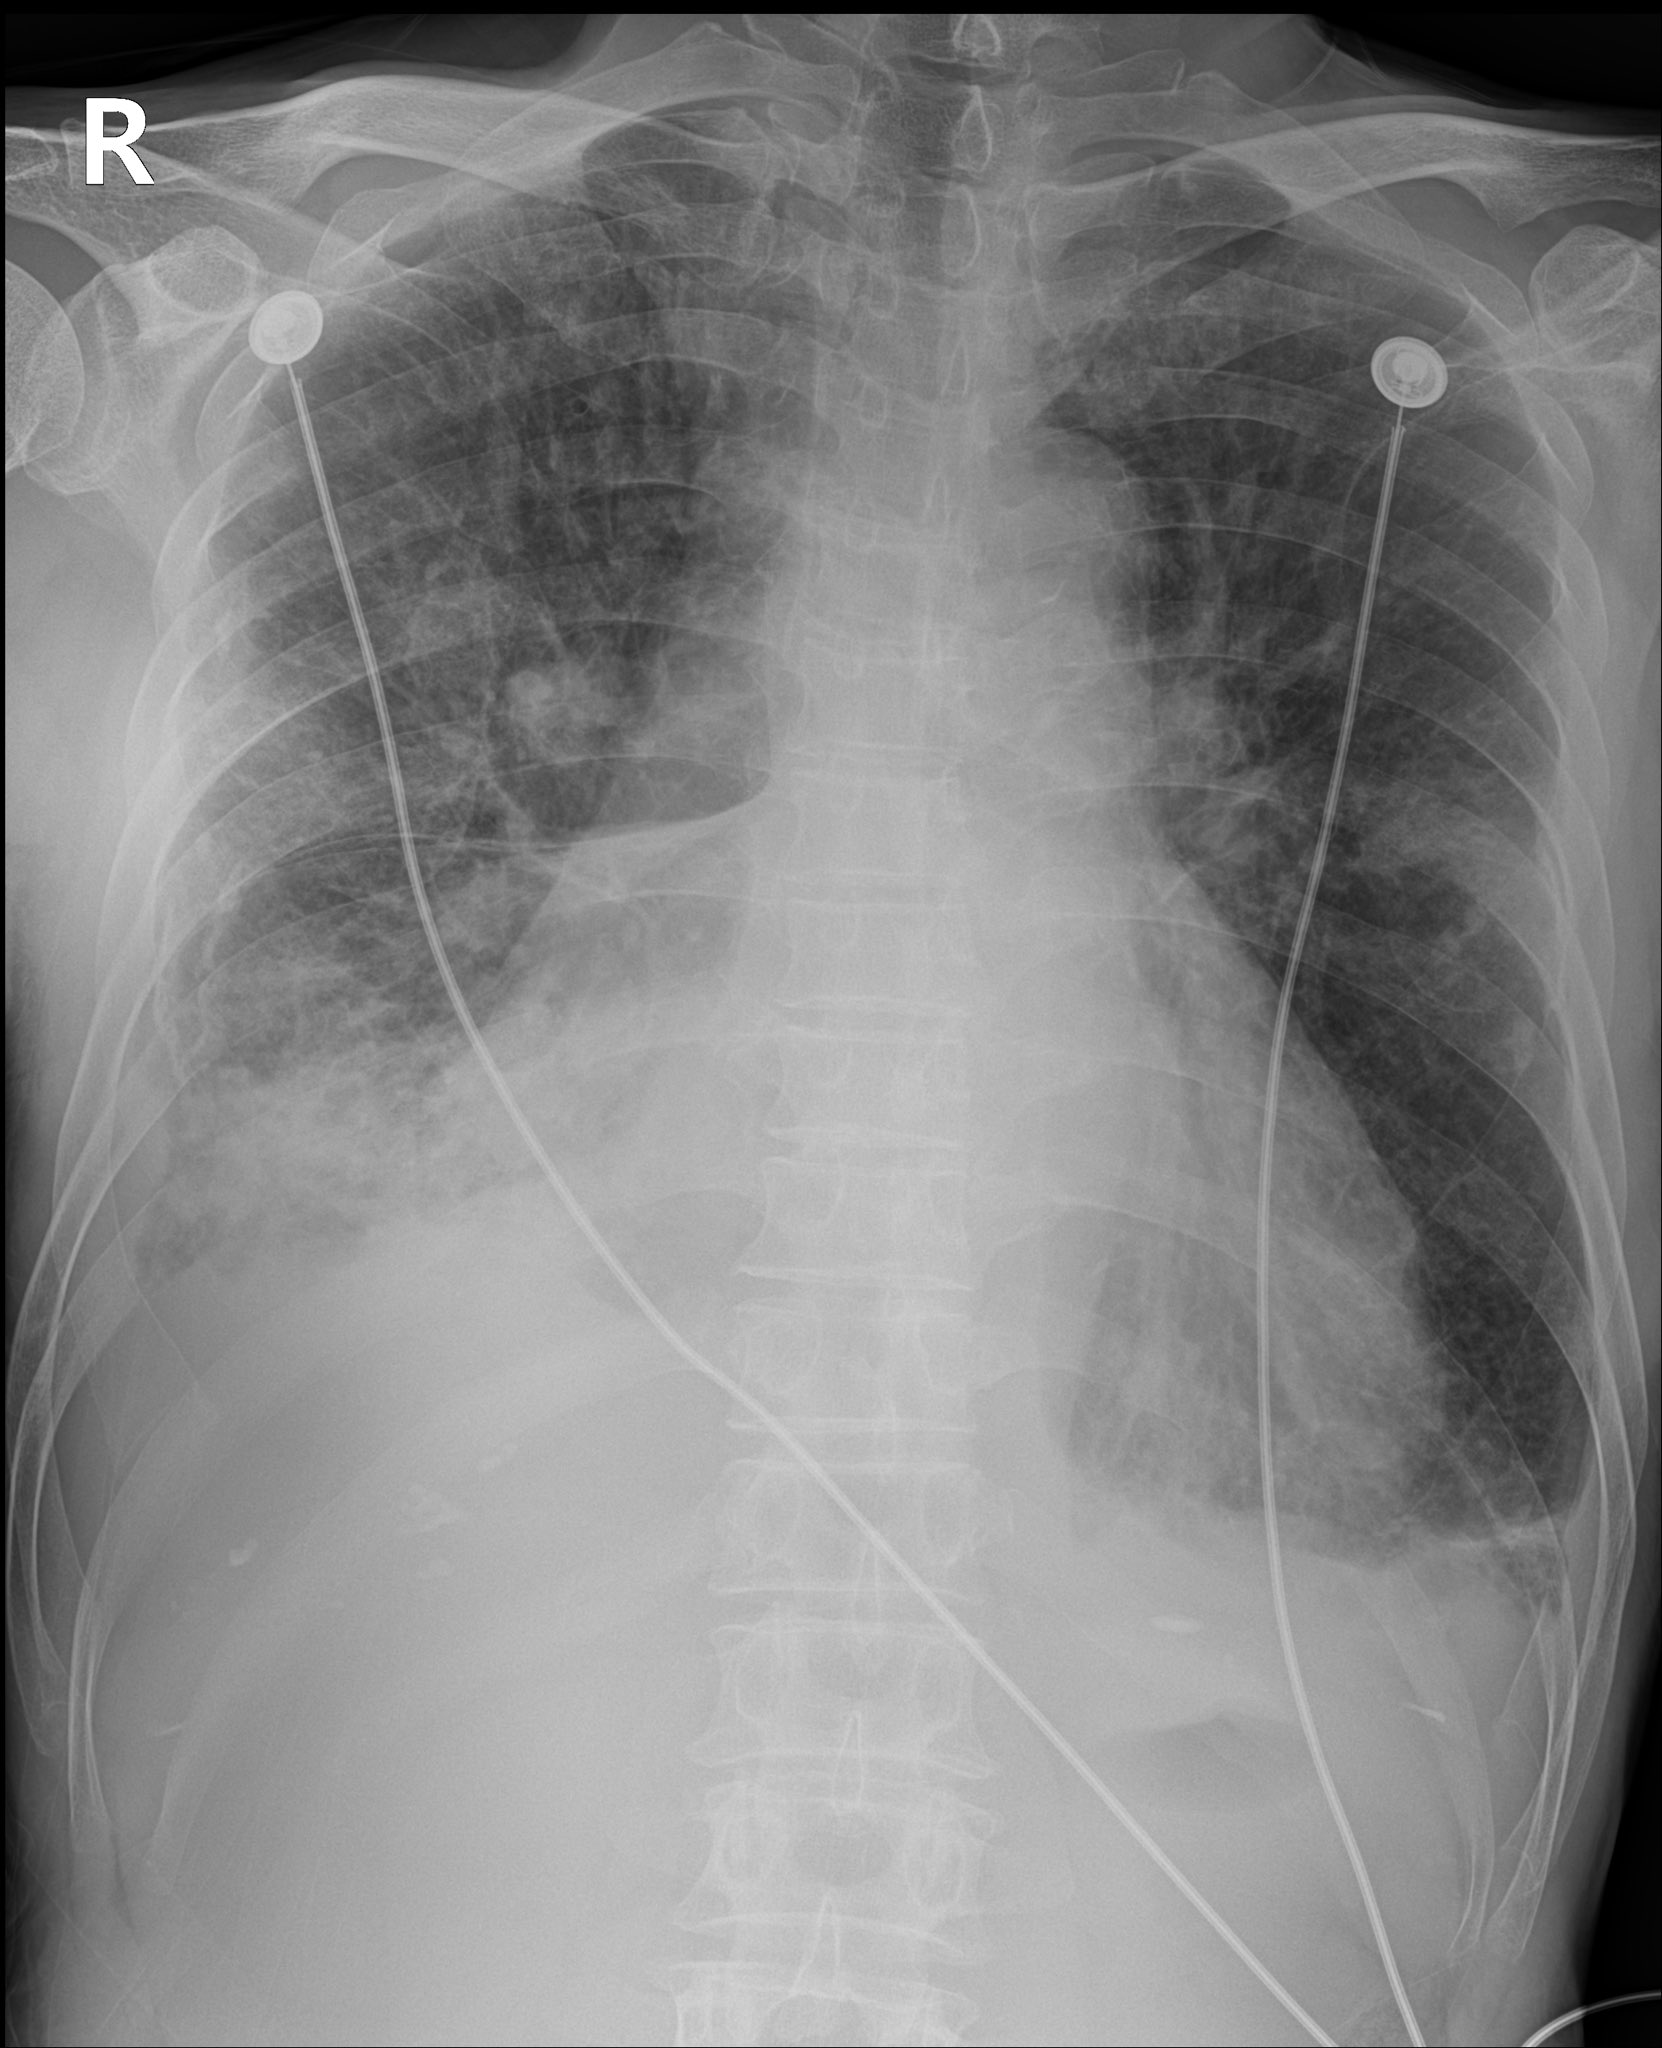

원인을 확인 하기 위해 시행한 흉부 chest x ray(chest AP)에서 우측 흉수(Pleural effusion)가 확인되었다.

1.1L의 흉수를 배액 한 이후 환자의 chest AP 사진을 보도록 하자.

불과 2시간 만에 다시 찍은 x ray라는 게 믿기지 않을 정도로 많이 좋아졌다.

환자분도 기관삽관을 할지 말지 걱정하던 상황에서 산소를 거의 끊을 정도로 증상이 많이 좋아졌다.